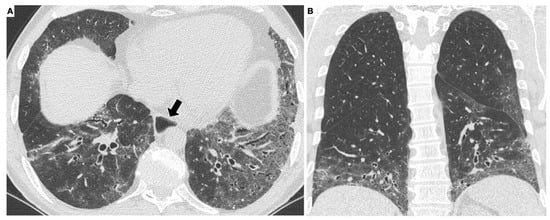

3.1. High-Resolution Computed Tomography in SSc-ILD: Qualitative Evaluation

3.2. High-Resolution Computed Tomography in SSc-ILD: Quantitative Evaluation

- Orlandi, M.; Landini, N.; Sambataro, G.; Nardi, C.; Tofani, L.; Bruni, C.; Randone, S.B.; Blagojevic, J.; Melchiorre, D.; Hughes, M.; et al. The role of chest CT in deciphering interstitial lung involvement: Systemic sclerosis versus COVID-19. Rheumatology 2021, 28, 615. [Google Scholar] [CrossRef]

- Goh, N.S.; Desai, S.R.; Veeraraghavan, S.; Hansell, D.M.; Copley, S.J.; Maher, T.M.; Corte, T.J.; Sander, C.R.; Ratoff, J.; Devaraj, A.; et al. Interstitial lung disease in systemic sclerosis: A simple staging system. Am. J. Respir. Crit. Care Med. 2008, 177, 1248–1254. [Google Scholar] [CrossRef]

- Yabuuchi, H.; Matsuo, Y.; Tsukamoto, H.; Horiuchi, T.; Sunami, S.; Kamitani, T.; Jinnouchi, M.; Nagao, M.; Akashi, K.; Honda, H. Evaluation of the extent of ground-glass opacity on high-resolution CT in patients with interstitial pneumonia associated with systemic sclerosis: Comparison between quantitative and qualitative analysis. Clin. Radiol. 2014, 69, 758–764. [Google Scholar] [CrossRef]

- Salaffi, F.; Carotti, M.; Bosello, S.; Ciapetti, A.; Gutierrez, M.; Bichisecchi, E.; Giuseppetti, G.; Ferraccioli, G. Computer-aided quantification of interstitial lung disease from high resolution computed tomography images in systemic sclerosis: Correlation with visual reader-based score and physiologic tests. Biomed. Res. Int. 2015, 15, 834262. [Google Scholar] [CrossRef] [PubMed] [Green Version]

- Salaffi, F.; Carotti, M.; Di Donato, E.; Di Carlo, M.; Ceccarelli, L.; Giuseppetti, G. Computer-aided tomographic analysis of interstitial lung disease (ILD) in patients with systemic sclerosis (SSc). Correlation with pulmonary physiologic tests and patientcentred measures of perceived dyspnea and functional disability. PLoS ONE 2016, 11, e0149240. [Google Scholar] [CrossRef] [PubMed]

- Ariani, A.; Silva, M.; Seletti, V.; Bravi, E.; Saracco, M.; Parisi, S.; De Gennaro, F.; Idolazzi, L.; Caramaschi, P.; Benini, C.; et al. Quantitative chest computed tomography is associated with two prediction models of mortality in interstitial lung disease related to systemic sclerosis. Rheumatology 2017, 56, 922–927. [Google Scholar] [CrossRef] [PubMed] [Green Version]